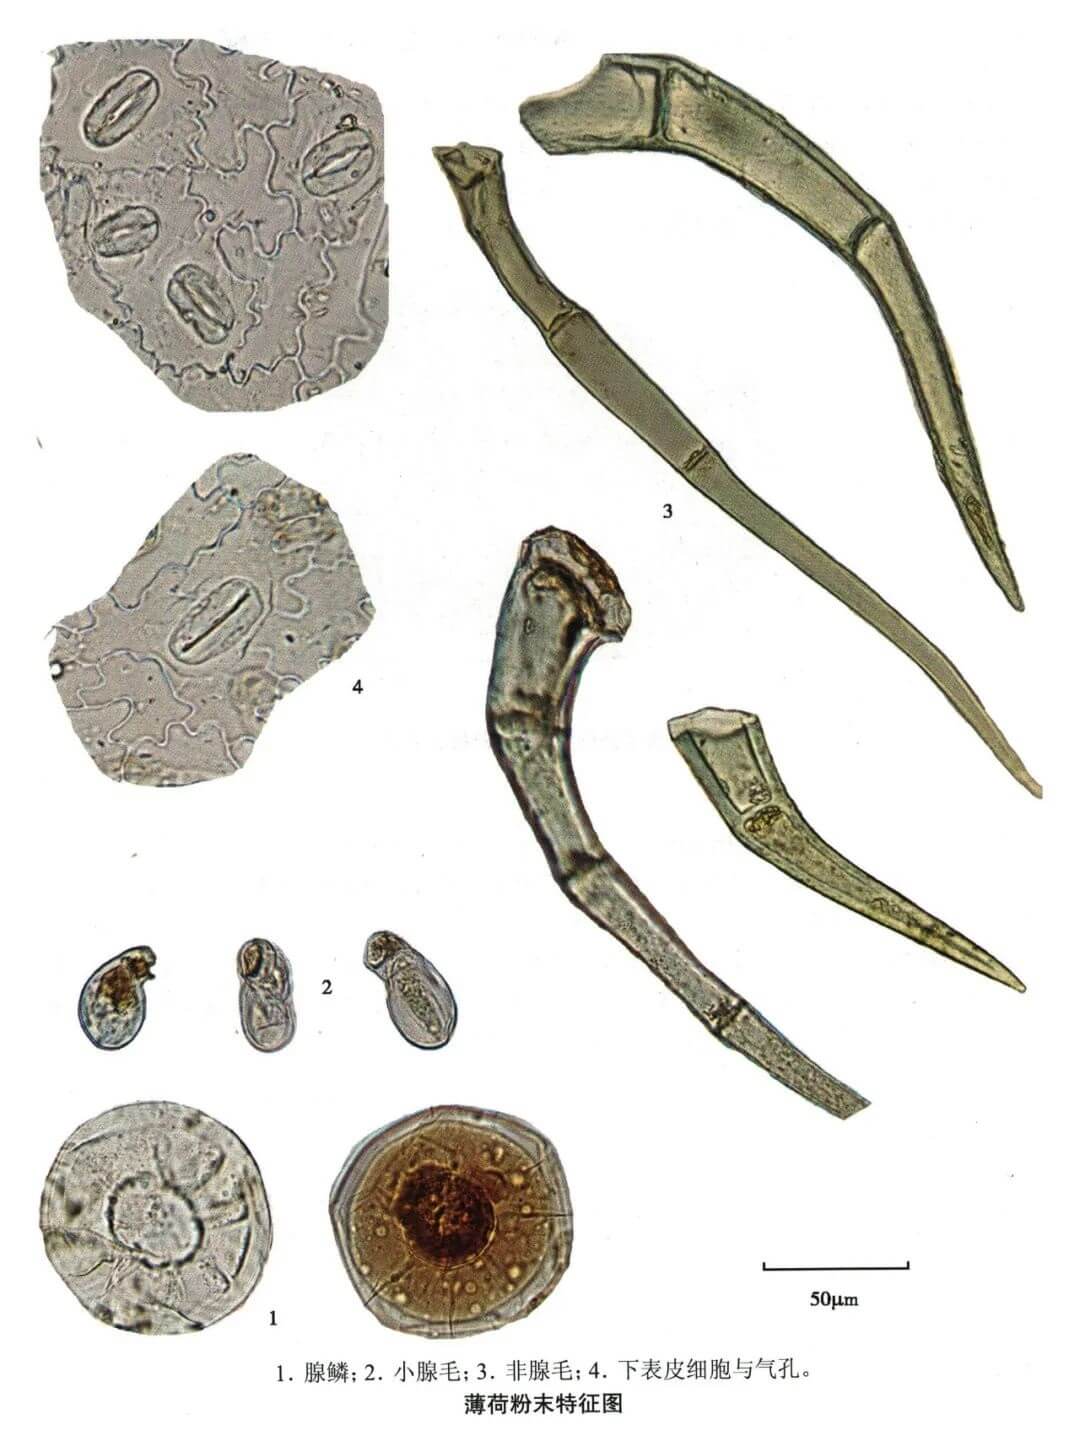

薄荷

| 薄荷 |

|---|

| 【参考文献】 《中药鉴定学》(康廷国主编) |

| 【显微鉴别】 腺鳞的腺头呈扁圆球形,由8个分泌细胞排列成辐射状,直径约90μm,腺头外围有角质层,与分泌细胞的间隙处有浅黄色油质,腺柄单细胞,极短,四周表皮细胞作放射状排列。表皮细胞壁薄,呈微波状,上、下表皮有直轴式气孔,以下表皮为多。小腺毛为单细胞头,单细胞柄。非腺毛由1 ~8个细胞组成,常略弯曲,壁厚,有疣状突起。 |

| 【显微重点】 腺鳞;叶下表皮细胞;腺毛。用稀乙醇装片,可观察到橙皮苷结晶。 |

| 【图谱来源】 《中药成方制剂显微图典》 |